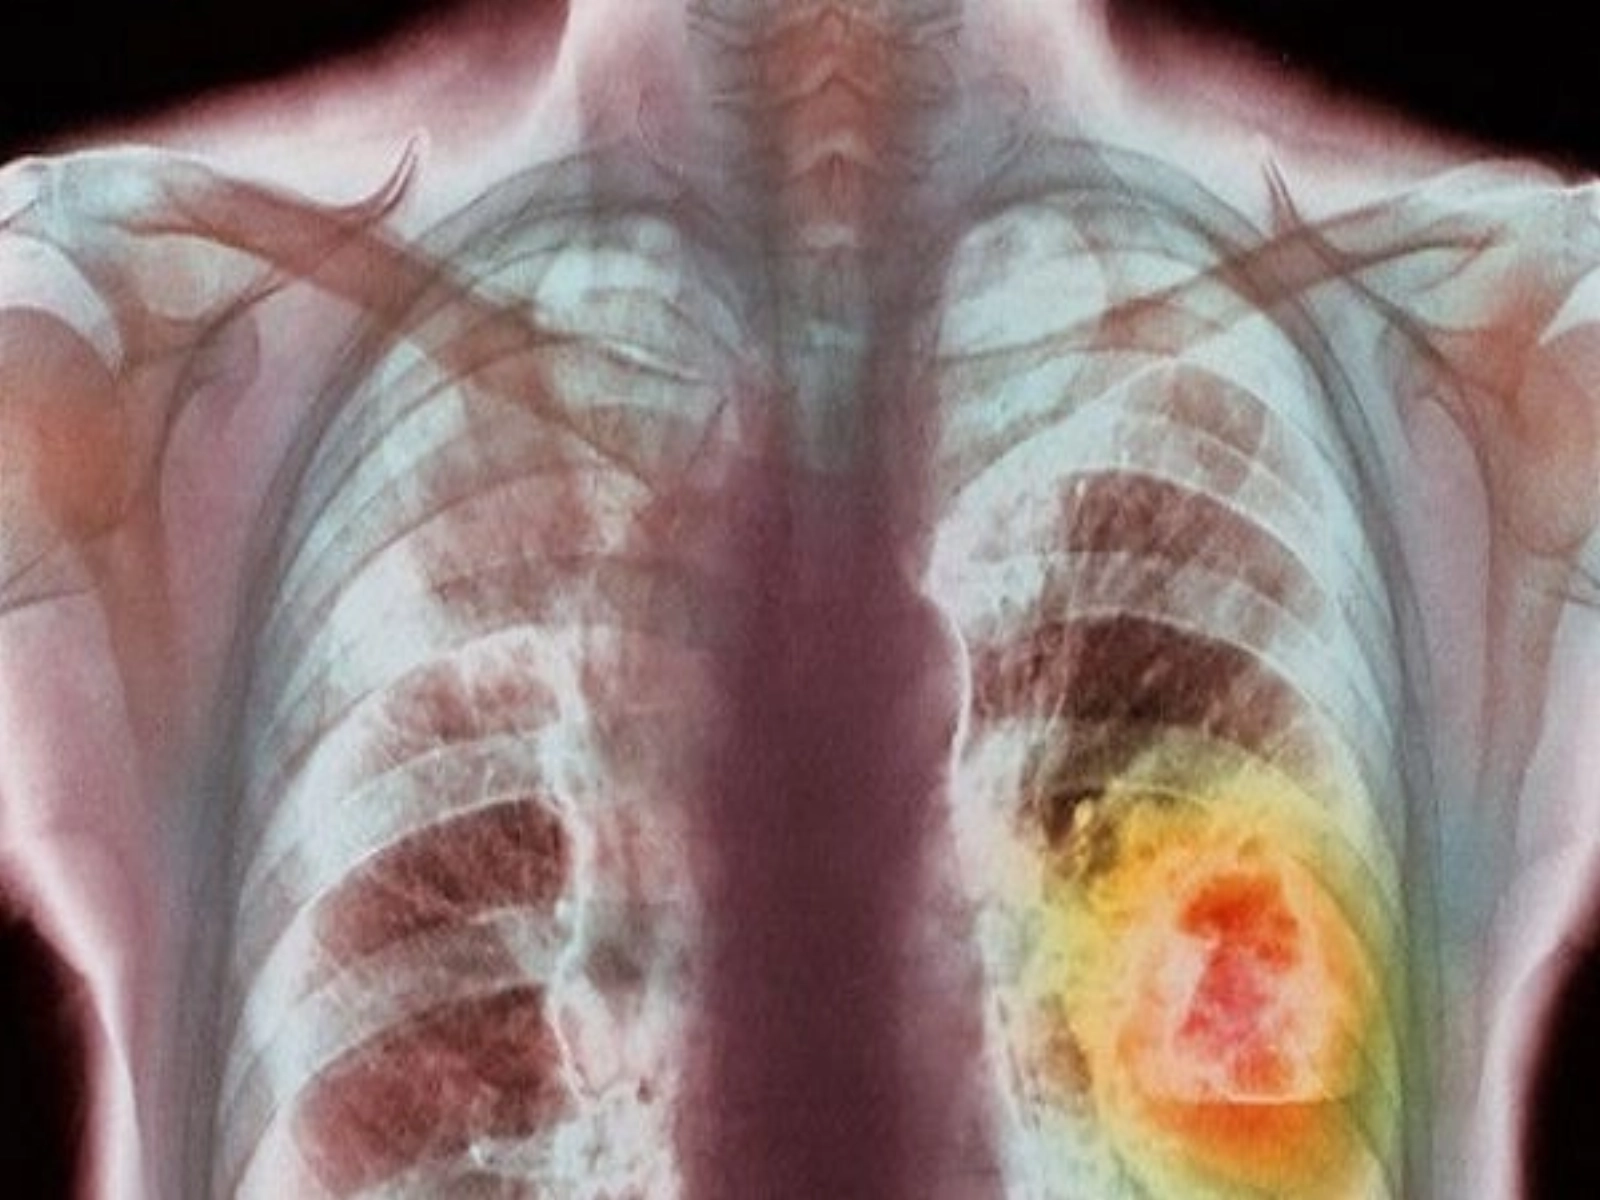

Un aparat de ultimă generație care ajută la depistarea precoce a trei tipuri de cancer, prin analize medicale, a fost cumpărat de o asociație din Prahova, județ cu 10.000 pacienți oncologici înregistrați. Este primul astfel de aparat din România care se folosește strict pentru pacienți, scrie Mediafax.

Aparatul este, de asemenea, singurul care lucrează în afară de biopsie solidă și biopsie lichidă. Are capacitatea de a determina din sânge modificările ADN-ului mutant pentru 3 tipuri de cancer: colorectal, pulmonar si de piele.